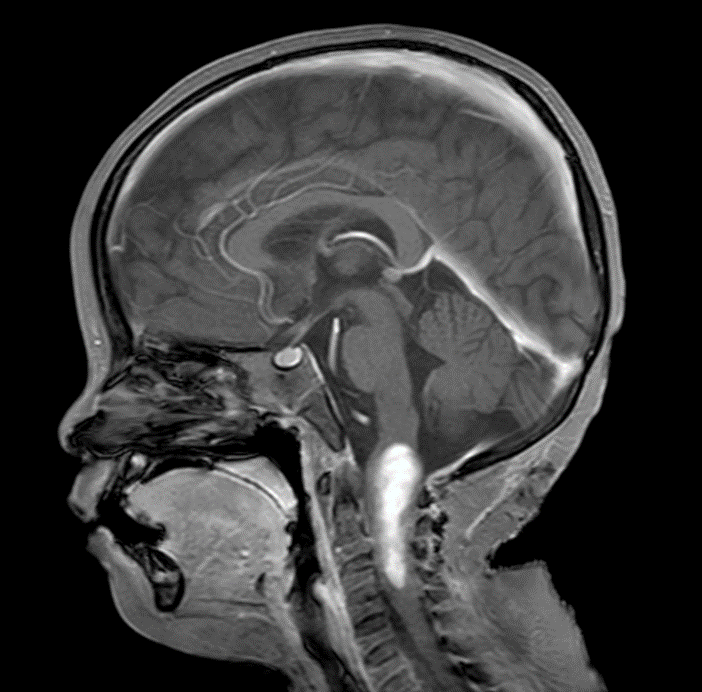

术前影像

术前MRI

怀着最后一线希望,阿什利一家跨海越洋,来到清华大学玉泉医院(清华大学中西医结合医院)脑肿瘤科求助。入院时,患儿右侧肢体活动严重受限,面瘫症状逐渐显现。影像检查显示肿瘤位于脑干中央,与周围重要神经结构和血管关系密切,手术难度极大、风险极高。